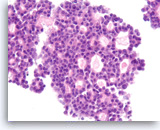

Pancreatic endocrine neoplasm #1,

Pancreas FNA, Direct Smear.

The aspirates show single and dyshesive clusters of neoplastic cells. The neoplastic cells show mild variation in size and have eccentrically located oval nuclei (plasmacytoid appearance). A few small cytoplasmic vacuoles are seen.

40X

Pancreatic endocrine neoplasm #1,

Pancreas FNA, Direct Smear.

The aspirates show single and dyshesive clusters of neoplastic cells. The neoplastic cells show mild variation in size and have eccentrically located oval nuclei (plasmacytoid appearance). A few small cytoplasmic vacuoles are seen.

40X